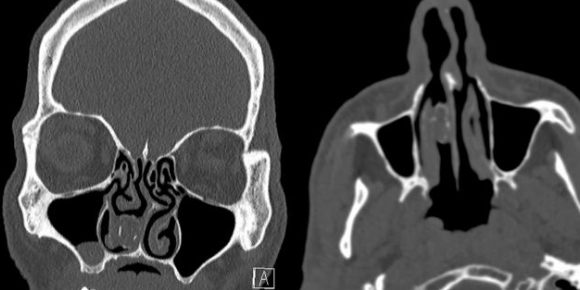

The 48-year-old man had been admitted to Westmead Hospital in Sydney, Australia, after complaining of headaches, according to a report published Oct. 25 in the journal BMJ Case Reports. A CT scan of his head revealed a “firm gray mass” in his right nasal cavity, and upon questioning, the man confirmed that he had experienced recurrent nasal infections and noticed an obstruction in his nostril.

Physicians called the mass a “rhinolith” — a term that translates to “nose stone” — meaning calcium and other minerals had built up around a “foreign body” in the man’s sniffer. They pulled the plug from the patient’s nostril and found that it appeared to be a “rubber capsule containing degenerate vegetable/plant matter.”